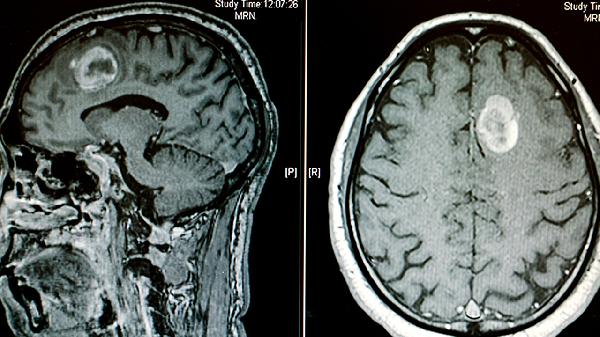

阿爾茨海默病、帕金森病等神經(jīng)退行性疾病可引起腦實(shí)質(zhì)萎縮,繼發(fā)側(cè)腦室被動(dòng)性擴(kuò)大?;颊叨喟橛姓J(rèn)知功能下降、運(yùn)動(dòng)障礙等表現(xiàn)。頭部MRI顯示腦溝增寬與腦室擴(kuò)大并存,治療以控制原發(fā)病為主。

腦室周圍出血或蛛網(wǎng)膜下腔出血后,血塊阻塞腦脊液通路或引起粘連性改變。出血急性期需控制血壓、降低顱內(nèi)壓,慢性期若形成腦積水可考慮腦室腹腔分流術(shù)。頭部CT能明確出血部位及腦室擴(kuò)張程度。